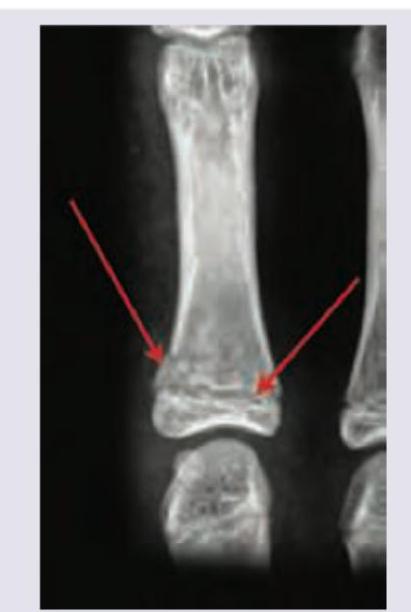

Explanation: ***Salter and Harris growth plate injury*** - The image clearly shows a **fracture through the growth plate** (physis) of a long bone, indicated by the red arrows pointing to a disruption at the metaphyseal-epiphyseal junction. This type of injury is classified by the Salter-Harris system. - Specifically, this appears to be a **Salter-Harris type II fracture**, where the fracture line extends through the physis and then exits through the metaphysis, leaving the epiphysis intact. *Morel-Lavallee lesion* - A Morel-Lavallee lesion is a **closed degloving injury** resulting from shearing forces that separate the skin and subcutaneous tissue from the underlying fascia. - It presents as a **seroma or hematoma** and is typically identified on MRI or ultrasound rather than a plain radiograph of bone. *Ulnar fovea sign* - The ulnar fovea sign is a clinical finding associated with **triangular fibrocartilage complex (TFCC) injuries** in the wrist. - It refers to localized tenderness upon palpation of the fovea, which is felt just distal to the ulnar styloid process, and is not a radiographic finding. *Rickets* - Rickets is a condition caused by a **deficiency of vitamin D, calcium, or phosphate**, leading to impaired mineralization of growing bone. - Radiographic features include **widened, cupped, and frayed growth plates**, bowing of long bones, and osteopenia, which are not the primary abnormalities depicted here.